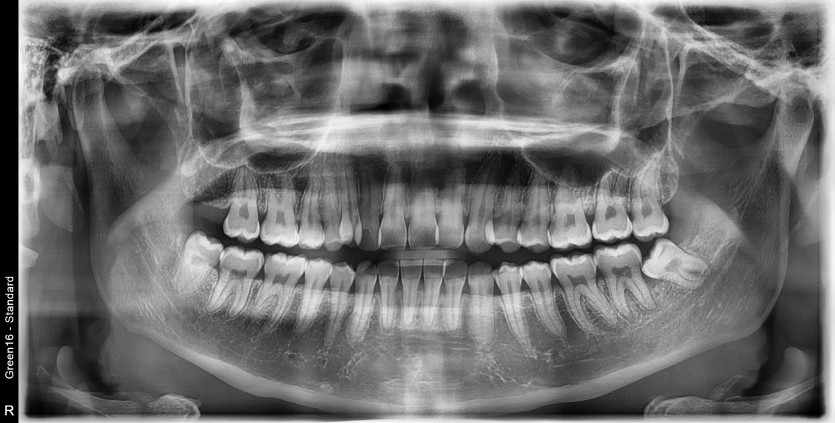

#28,38,48 사랑니 발치

구강 외과 전문의가 당일 발치했습니다.